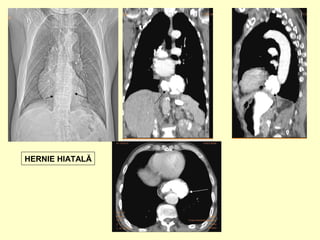

HERNIE HIATALĂ

Hernia hiatală

• Hernie a unei portiuni de stomac in mediastin

prin hiatusul esofagian al diafragmului

• Prin rostogolire (paraesofagiana)fornixul

herniază paraesofagian, esofag de lungime

normală, cardia în abdomen.

• Prin alunecare-esofag cu lungime normala,

fornix si cardia în torace.

• Hernie hiatala cu esofag scurt(brahiesofag),

cardia intratoracic.

• Radiografia toracica PA si profil

• Examen cu substanta de contrast tub

digestiv (clinostatism ,Trendelemburg)-

sediul orificiului cardial,dimensiunea

inelului hiatal ,pozitia esofagului

abdominal ,unghiul HIS)

• CT cu admininstrarea unei mici cantitati

de contrast oral in timpul examinarii